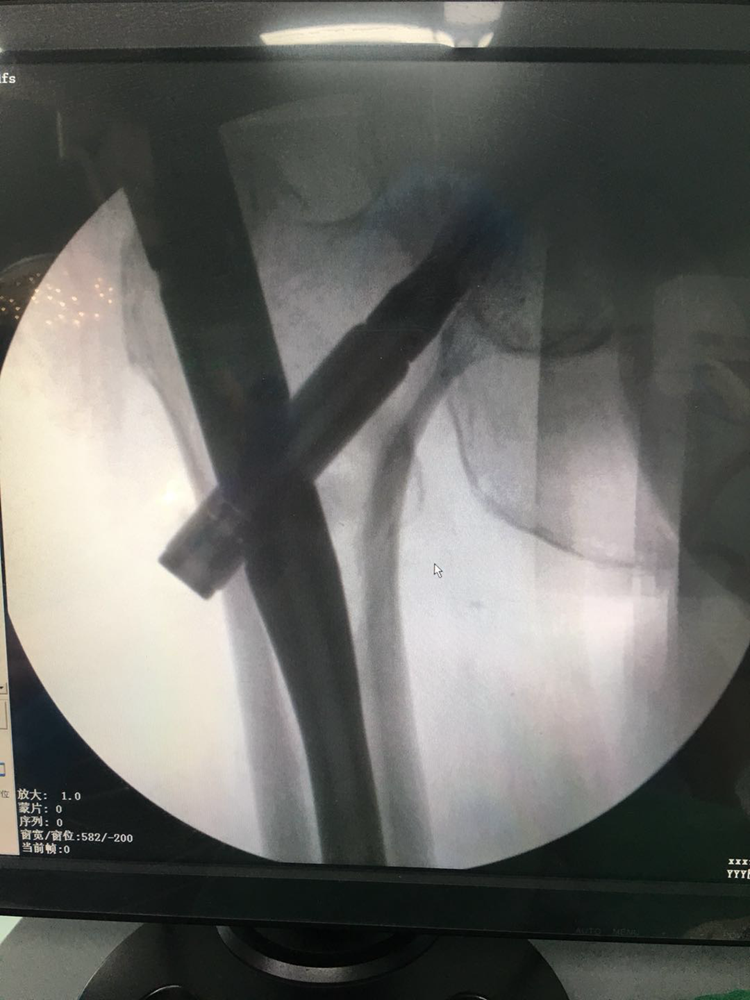

近日,我院骨伤科顺利为一名83岁高龄的股骨粗隆间骨折患者完成手术。该患者因摔倒致左股骨粗隆间骨折遂到我院求诊。入院行相关检查后,主管医生反复与患者及家属沟通治疗方案,但患者同时合并多种基础疾病,手术风险大。髋部骨折选择保守治疗,往往会增加高龄老人死亡率。骨伤科主任颜昌能立即邀请相关科室会诊,并组织科室医务人员进行讨论,决定为患者行左股骨粗隆间骨折PFNA内固定术。为缩短手术时间,术中未使用牵引床,而是采用特殊体位固定,更加有利于老年患者的康复。经过医务人员一小时的努力,顺利为患者完成手术,且术后恢复良好,得到患者及家属的一致好评。(投稿/骨伤科 喻鑫泉)

2.PFNA术是股骨粗隆间骨折髓内固定装置中的一种。生物力学证实:髓内固定系统较髓外系统力臂短,比髓外固定更稳定。PFNA坚持AO坚强内固定的理念,生物力学稳定,其适用于绝大多数股骨粗隆骨折。PFNA为中心型固定,受力分散均匀,而且基本上不受小粗隆股骨矩破坏的影响。因为其受力由髓内钉主钉分散承担,股骨矩的完整与否关系不大。而且其具有手术创伤小、程序步骤简化,缩短了手术时间、出血量少等特点。